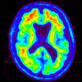

Amyloid PET scan for diagnosis

State-of-the-art imaging of the head and neck is offered with CT, MRI, and molecular modalities such as PET. The group has expertise in the full array of neurologic disease, including brain tumors, stroke and other vascular disorders, spine disease, neurodegenerative diseases, and brain malformations.

Nuclear medicine helps doctors to determine the causes of a medical problem based on functional information about tissues organs or bones (via for example a nuclear medicine bone scan). We provide expert diagnosis and treatment including:

• Brain

The San Francisco VA has substantial imaging infrastructure in place to support advanced imaging programs. This includes: 3T and 7T MRI scanners that are dedicated for research; clinical 3T and 1.5T MRI scanners; PET-CT; state-of-the-art CT scanners; and US scanners.